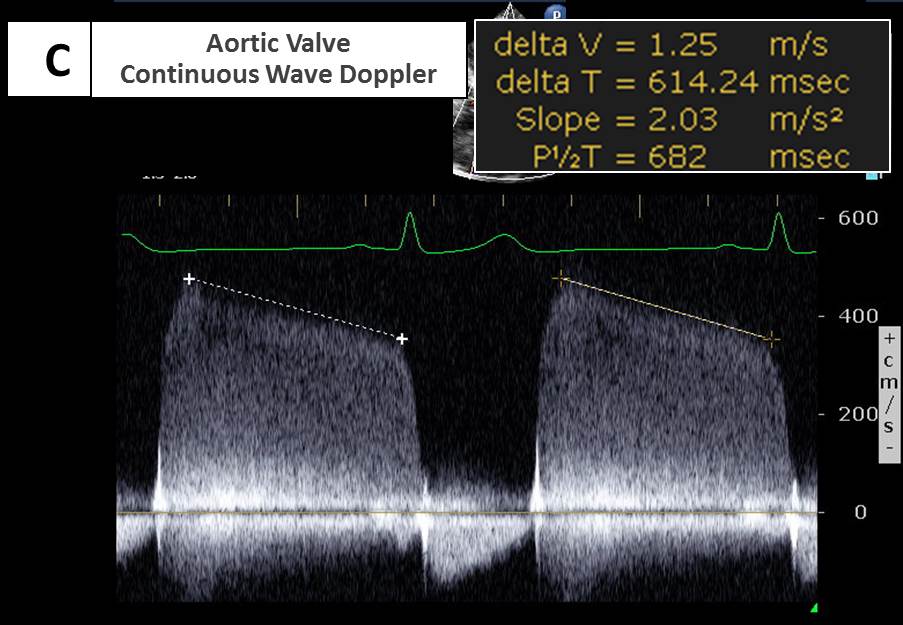

Explanation for Answer C

Due to a large regurgitant orifice, there is rapid equalization of diastolic pressures between the ascending aorta and the left ventricle. This leads to rapid deceleration and a short pressure half-time of the aortic regurgitant jet on spectral Doppler tracings, as shown in the lower panel of Figure 8. This is in contrast to chronic and/or less severe AR in which the deceleration slope is less steep and the pressure half-time is typically longer. Thus Figure 3 is NOT consistent with severe acute AR, and answer C is the correct answer.

As stated in the 2017 American Society of Echocardiography guidelines for evaluation of native valvular regurgitation, a pressure half-time >500 msec suggests mild AR, and <200 msec suggests severe AR. However, pressure half-time is determined not only by the size of the aortic regurgitant orifice but also by compliance of the left ventricle. Thus, patients with severe chronic AR and a compliant left ventricle may have a pressure half-time in the ''moderate'' range. In contrast, in patients with severe diastolic dysfunction and only mild AR may have short pressure half-time. Because vasodilator therapy decreases diastolic blood pressure independent of the AR, pressure half-time method is less useful for monitoring AR in patients receiving vasodilators.

Figure 8